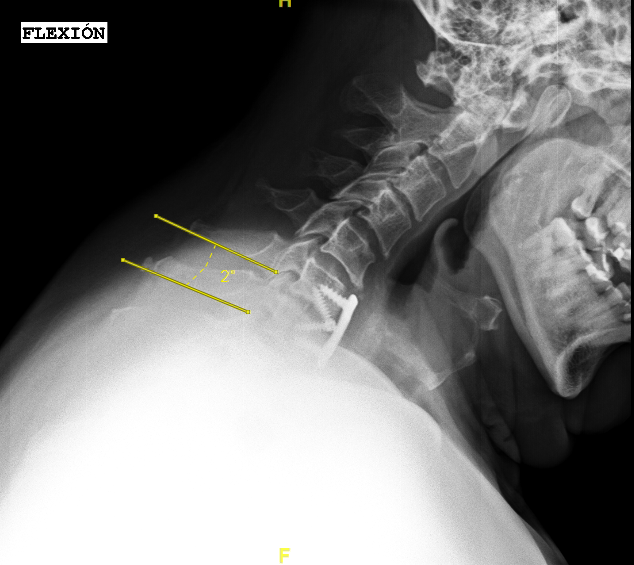

Las RX dinámicas reflejan la ausencia de fusión C6-C7

Las RX dinámicas (6m postop) demuestran estabilidad de la artrodesis